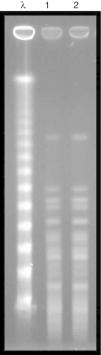

Microbiological aspectsBacterial identification was performed by matrix-assisted laser desorption/ionization time-of-flight mass spectrometry (MALDI-TOF/MS) technology, using Vitek MS® system (bioMerieux, Marcy-I’Étoile, France), and the antimicrobial susceptibility profile was determined using the Vitek® 2 system (bioMerieux). The minimum inhibitory concentration (MIC) for polymyxin B was defined by broth microdilution (Probac, Brazil). The two strains evaluated (donor and recipient) exhibited high levels of resistance to cefepime, cefoxitin, ceftazidime, ceftriaxone (MIC≥64μg/mL), ertapenem (MIC≥8μg/mL), imipenem (MIC, 8μg/mL), meropenem (MIC≥16μg/mL), ciprofloxacin (MIC, ≥4μg/mL), gentamicin (MIC≥16μg/mL), and tigecycline (MIC, 4μg/mL) following the breakpoints established by CLSI, 2016.3 Resistance to polymyxin B (MIC, >64μg/mL) was established using the EUCAST breakpoint, 2017.4 Amikacin was the only susceptible drug (MIC, 4μg/mL). The presence of the blaKPC resistance gene was detected in all strains evaluated,5 and the molecular gene identification using Sanger sequencing exhibited 100% homology with the enzyme KPC-2. The genetic similarity between strains was established by pulsed field gel electrophoresis (PFGE) using the SpeI restriction endonuclease, demonstrating an identical PFGE pattern (Pattern A) between the donor and recipient strain (Fig. 2). Multilocus sequence typing (MLST) analysis also identified the same sequence type (ST 437) from the donor and the recipient strains, and eBURST analysis (http://eburst.mlst.net) revealed that ST 437 belonged to clonal complex CC 258.